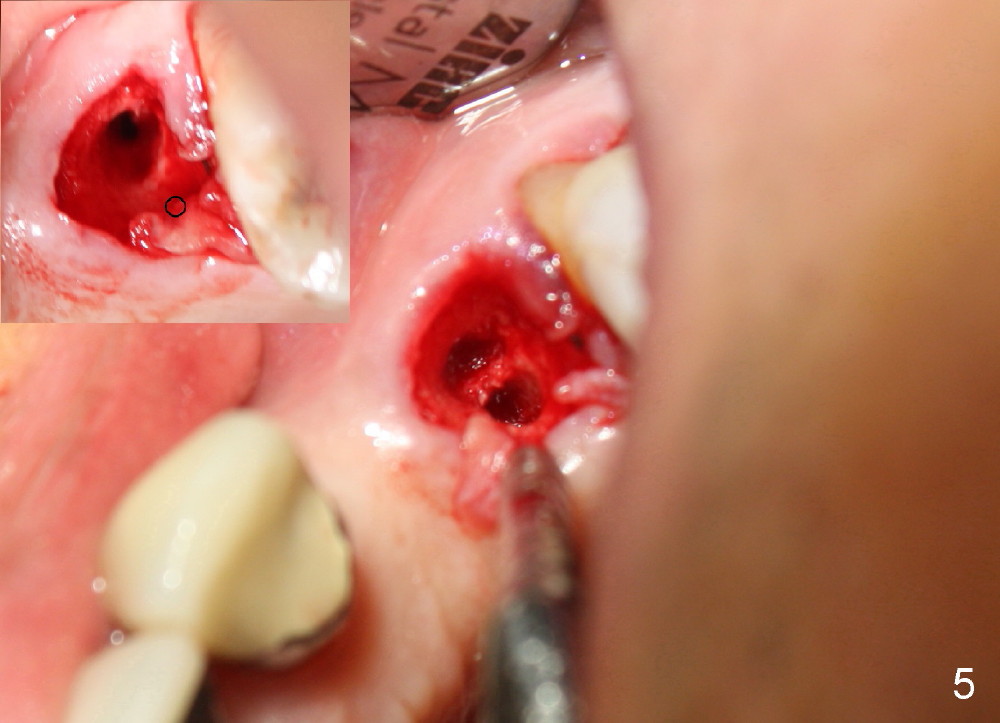

The anterior retainer is kept as a crown at #11 (Fig.2: C), whereas the residual root at the site of #13 is extracted with apical perforation (Fig.3 ^). It is confirmed by Fig.4 (<). To close the perforation, an osteotomy is initiated on the palatal wall of the socket with a 2 mm osteotome (Fig.5 insert: circle). As the osteotomy is being enlarged by a 3 mm osteotome, the bone between the original socket and the osteotomy is being pushed buccally. The former is being closed (Fig.5). The osteotomy is finished with combination of osteotomes and reamers. Fig.6 shows that a 5x14 mm tap is inserted at the site of #13 and that the sinus floor is lifted. In fact the sinus membrane is partially torn at the osteotomy, which is repaired by insertion of Colla-form Dressing (Impladent), followed by autogenous bone (harvested from reamers) mixed with Osteogen (Impladent). A 5x14 mm implant is placed at the site of #13 with insertion torque more than 60 Ncm (Fig.7: I). An incision is made at the site of #12 to start osteotomy with insertion of a parallel pin (Fig.7 P). A 3 mm reamer is kept in place for position confirmation (Fig.8 R). Due to ridge atrophy (Fig.2 arrowheads), a much smaller, but longer implant is placed at the site of #12 (Fig.9: 4x17 mm). The autogenous bone harvested from #12 osteotomy is placed in the buccal gap of #13, followed by insertion of Colla-form Dressing (Fig.10 M). To protect the membrane, a short abutment (4x3 mm) is temporarily placed (Fig.9,10 A) and perio dressing (Fig.9 D) is applied around the abutment and the interproximal areas of the neighboring teeth. Usually perio dressing dislodges around 1 week postop, particularly for a large edentulous space. In this case, the dressing is quite stable 11 days postop: the abutment (Fig.11 A) appears to contribute to retention of the dressing (D).